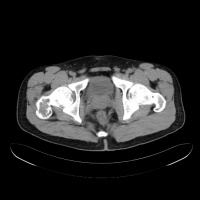

常发生于5到15岁的儿童,男性发病多于女性,比率约为2:1。病变部位多在长骨的干骺端。最常见部位为肱骨近端,其次为股骨近端。活动性(active相对具有侵袭性的)骨囊肿靠近骨骺区,随着儿童年龄增大,病灶会逐渐远离骨骺,成为非活动性(inactive)。在年龄超过17岁的患者,病变会在非长管骨发生,如跟骨、骨盆等。

有经验的骨肿瘤医生仅凭X线平片就可以作出骨囊肿的临床诊断。病变灶为边界清晰的液性低密度灶,四壁为薄层的硬化灶壳。病变灶略向近骨骺的干骺部位扩大。病灶非偏心性,也不破坏骨外壳,更不会突破骨质形成骨膜外反应骨,除非是在病理骨折后的愈合期。有时脱落的骨皮质成份落入囊腔中,X片显示被称为“落叶征”(FallenleaforFallenfragment)。当病灶发生在骨盆,CT扫描对病灶部位及囊肿形态的判断有价值。MRI可以明确囊内富含的液性成分。骨ECT扫描表现为外周薄的浓集而中央病灶冷区。

二CT:

1.骨囊肿一般多呈圆形、卵圆形低密度骨质缺损,边缘清晰,无硬化。

2.局部骨皮质变薄呈囊性膨胀。

3.少数囊肿内可见骨性间隔,呈多房改变。

4.骨囊肿内的CT值多为水样密度,有出血时密度可升高。

5.增强扫描囊肿不强化。